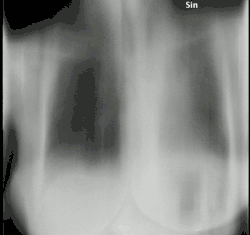

Tomossíntese

Tomossíntese é um método para obtenção de tomografia de ângulo limitado com níveis de radiação compatíveis com a radiografia convencional.[1]